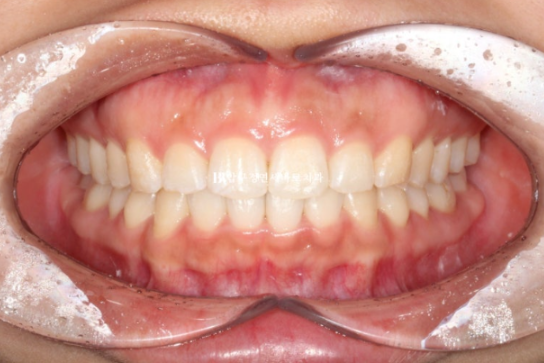

24.10

24.02~24.10

뻗쳐있던 앞니 각도는 좋아졌고

공간도 깔끔하게 모아졌으며 배열도 좋습니다.

앞니를 뒤로 넣을 때 단순 뒤로만 움직이는 것이 아니라 위로 올리면서 함입하며 넣었기에 잇몸 노출량도 소량 줄었습니다.

일자로 떨어지는 앞니 각도는 세련된 인상을 줍니다

8개월 간 변화 소개입니다.